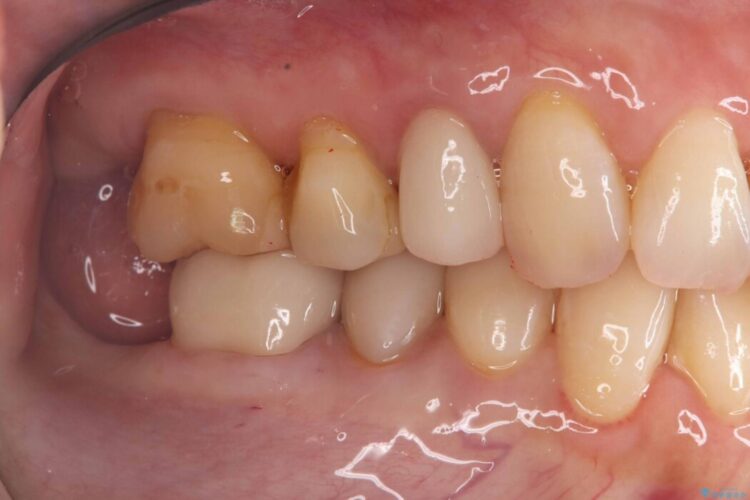

そのため今回は、歯をしっかり保護し、長期的な安定を図るために、オールセラミッククラウンによる修復を行いました。

クラウンにすることで、噛む力を分散しながら歯を保護できるため、再び割れてしまうリスクを大きく下げることが可能です。

- 概算治療費:15.4万円(税込)(オールセラミッククラウン14.3万円+仮歯1.1万円)